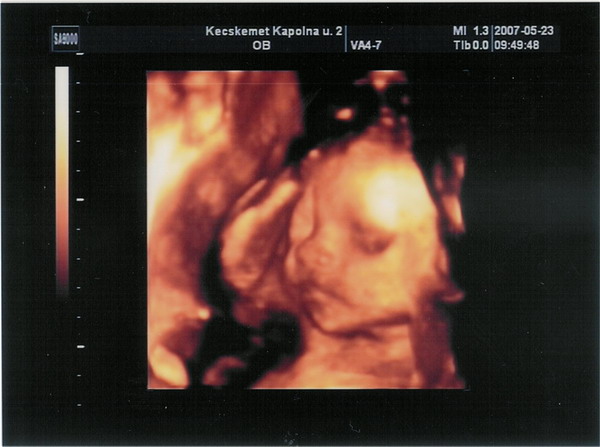

Megvolt ma a 4D!KISFIÚÚÚÚÚÚÚ Very Happy Very Happy Very Happy

Kecskeméten voltunk,egy aranyos doktornőnél.Nagyon jó volt a vizsgálat,bár kicsit rövid ideig tartott.A felvétel 10 perc kb.,az egész lement 25 perc alatt.Viszont olyan szempontból elégedett vagyok,hogy minden csontját és porcikáját nagyon átnézte,lemérte és kaptunk egy részletes leletet róla.Szerencsére minden rendben. Very Happy

Ja,még van valami:a méhemet is teljesen átnézte és végre van egy biztos diagnózis.Nem kétszarvú mégsem,hanem sövényem van.Ezt is kileletezte.

Zétikénk: